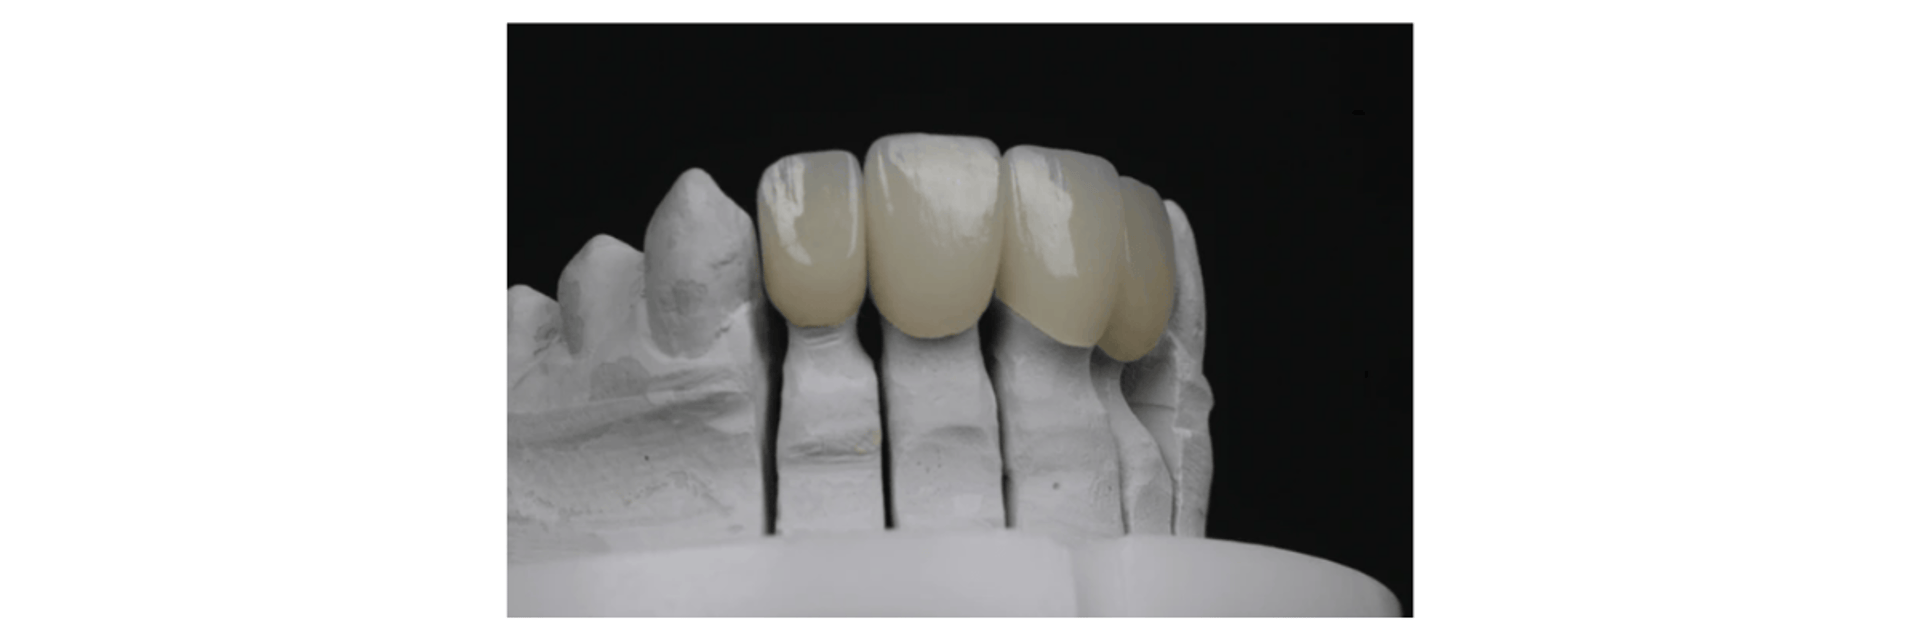

Fabricación (Producción CAM): Se realiza por medios digitales, ya sea por sustracción (fresadoras de circonio/cerámica) o adición (impresoras 3D).